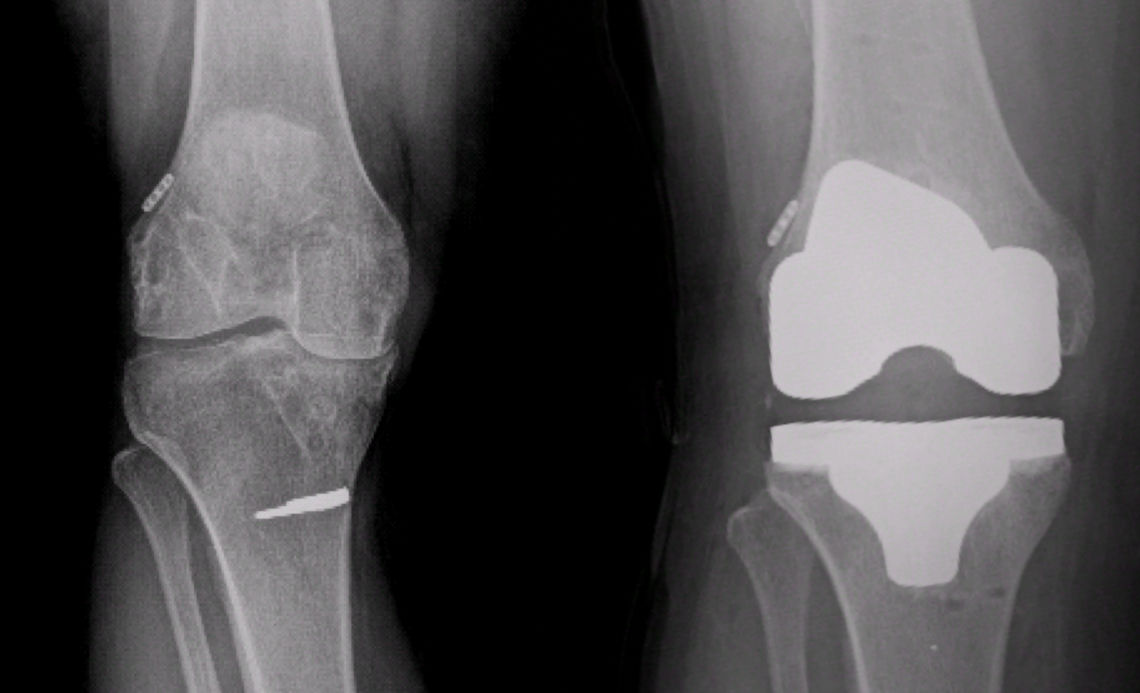

Ameliyatın ertesi gününde, aktif ve yardımlı diz hareketleri bir fizyoterapist gözetiminde başlanır. Bunun için fizyoterapist yardımı veya sürekli pasif hareket (continious passive motion, CPM) cihazı ile istenen açılarda diz hareketleri yapılır. Doktorunuz gerekli görürse, bu cihazı evde kullanmak üzere kiralayabilmeniz mümkündür. Eğer dren yerleştirilmişse, 24 saat civarında çıkartılır. Röntgen kontrolünüz yapılır (Resim 5).

Resim 5: Dizde ileri derecede aşınması olan bir hastanın ameliyat öncesi ve robotik total diz protezi sonrası röntgen grafileri.